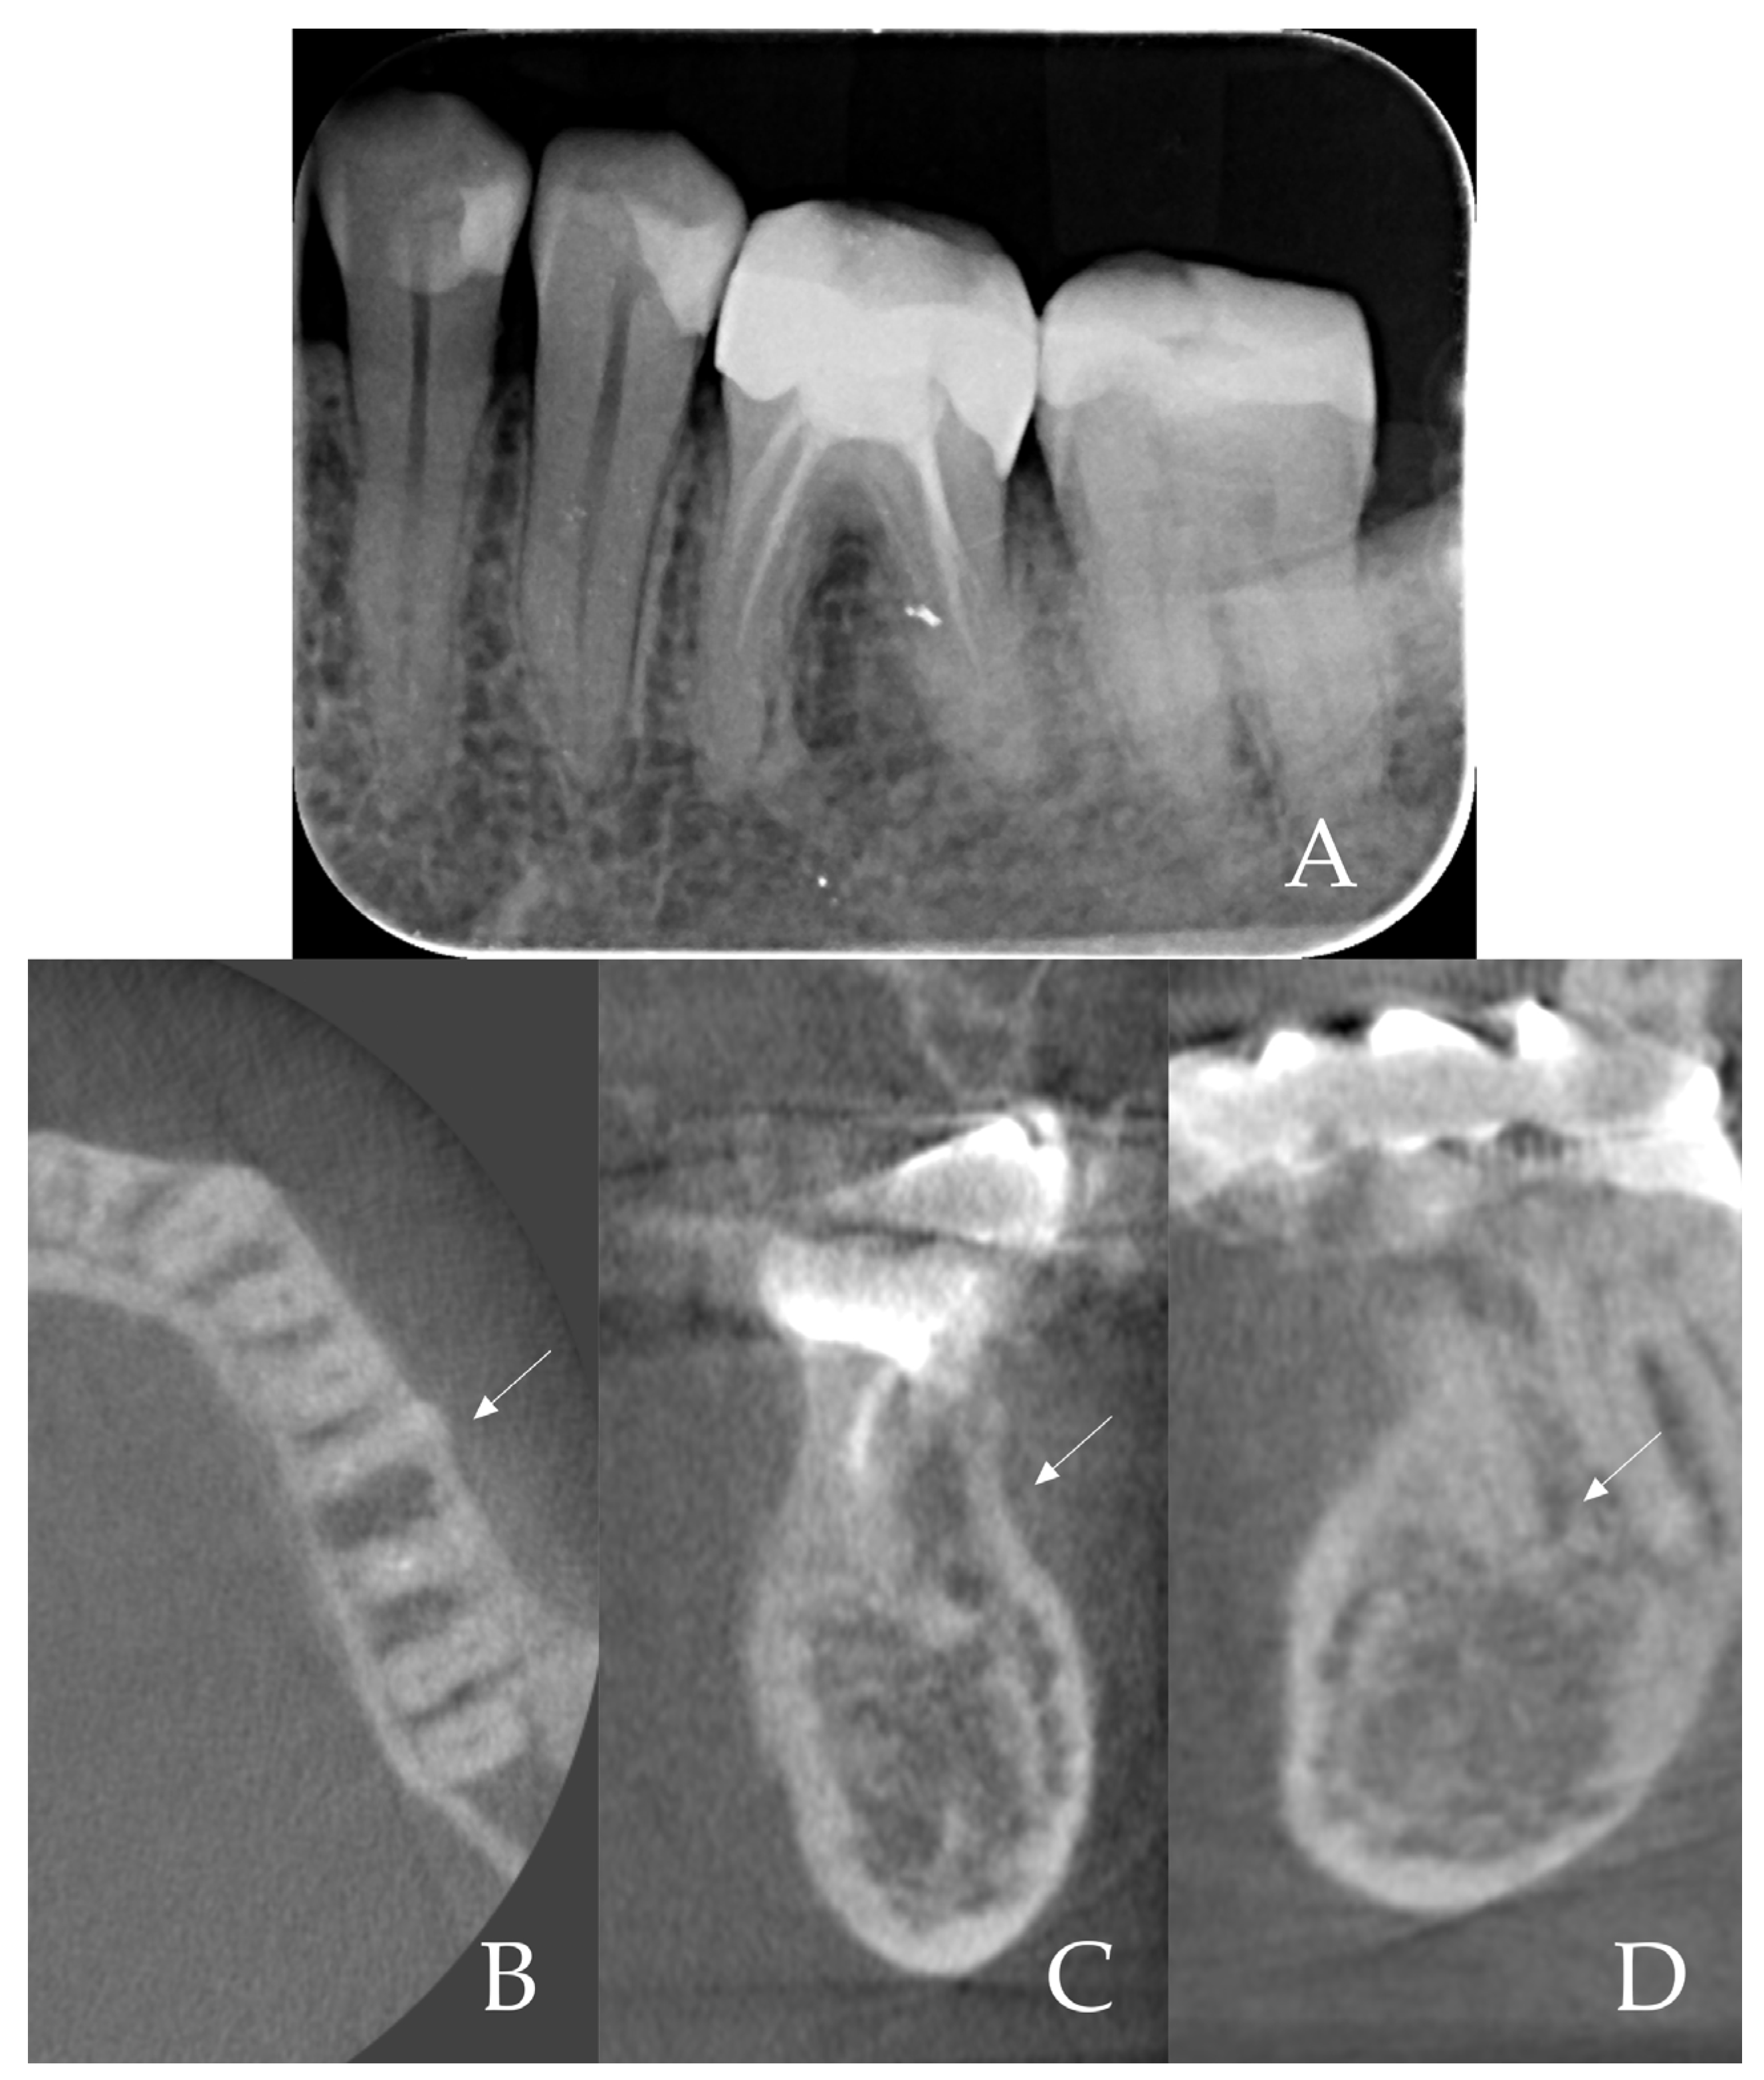

- 1.

- Root sectioning: After performing mandibular nerve block anesthesia, the crown of tooth #36 (Figure 2A) was removed (decoronation was performed) (Figure 2B). The mesial and distal roots were then separated buccolingually using a long-shanked, straight diamond bur in a high-speed handpiece with copious irrigation (Figure 2C). The preoperative CBCT was consulted to guide the depth and orientation of the cuts, accounting for the roots’ length, curvature, and angulation.